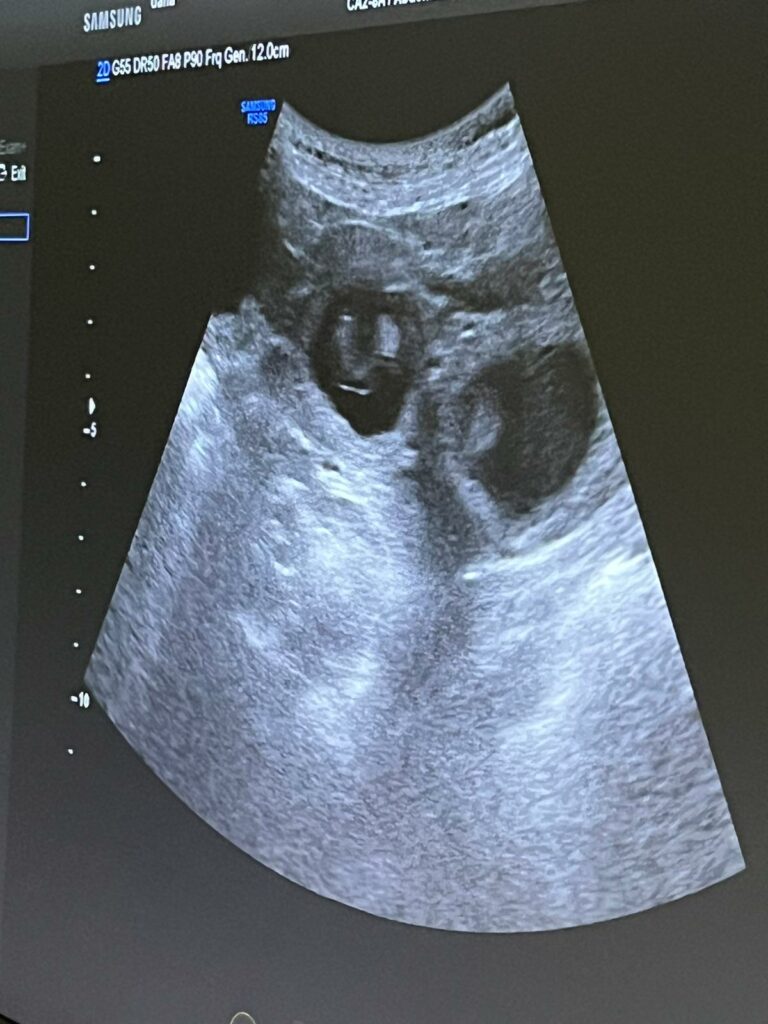

Vandaag was dan eindelijk de echo om te zien of Mildred daadwerkelijk drachtig is en al meteen zagen we pupjes in beeld verschijnen!! Fantastisch!! Ik was er niet helemaal zeker van, zij was de vorige keer de hele dracht ziek, nu heeft ze nergens last van. At ze de vorige keer nagenoeg niets, nu heeft ze voortdurend zin in met name lekkere dingen….. zag wel dat de tepels dikker werden en voelde ook al een buikje…..maar ja, zij gaat meestal na de loopsheid de schijndracht in en dan hebben ze dat ook. Helemaal blij dus dat ze drachtig is en er een flink aantal pupjes voorbij kwamen. Dat hebben Gahan en Mildred super gedaan!! 🥰 Er wordt erg naar de pupjes uitgekeken, ook in Noorwegen is de blijdschap groot ❣